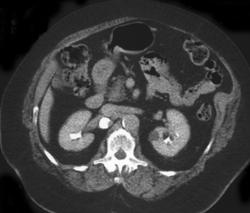

Multilocular Cystic Nephroma